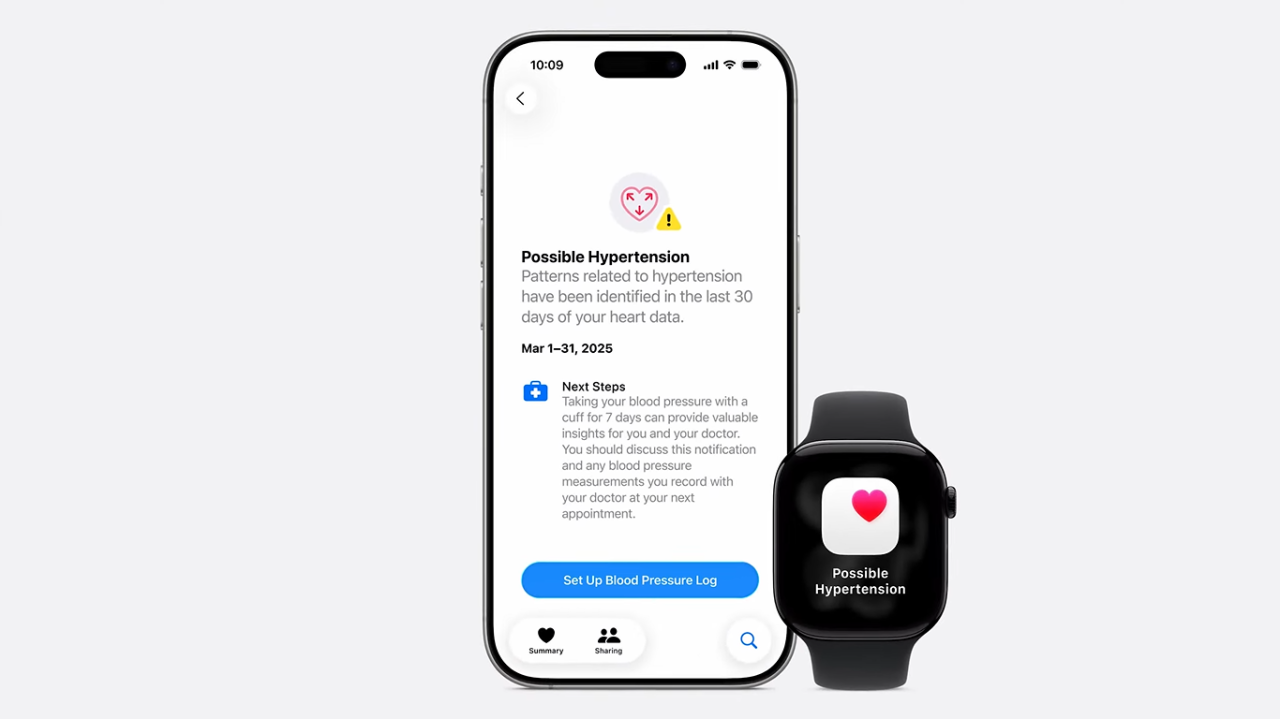

Apple Watch Series 11

Apple представила нове покоління розумних годинників, які стали найтоншими і найлегшими за всю історію бренду. Корпус отримав збільшену стійкість до подряпин – удвічі вищу порівняно з Series 10, а новий чип S11 забезпечує роботу всіх AI-функцій watchOS 26, включно з поліпшеним опрацюванням даних про здоров’я та активність.

У годинник додали нові функції для здоров’я: виявлення гіпертонії та оцінка сну Sleep Score на основі фаз сну, регулярності відходу до сну і тривалості пробуджень.